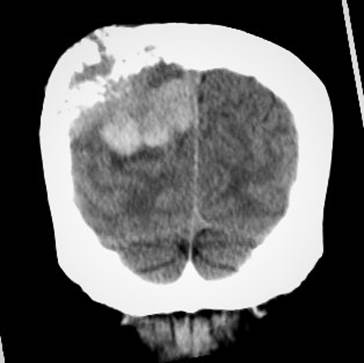

CASO 2 (METASTASIS CEREBRAL)

Paciente de 68 años de edad, que ingresa referida de otra institución por presentar más tumoral en región occipital derecha de gran tamaño dura muy adherida, dolorosa con circulación colateral; paciente desorientada en tiempo y espacio, irritable y poco colaborativa, en algunas ocasiones ha presentado convulsiones tónico clónicas. Además, presenta masa cervical voluminosa, a nivel tiroidea, dura, adherida a estructura aéreas y vasculares.

Se toma biopsia con aguja gruesa de lesión tumoral cervical y tumoración occipital encontrando carcinoma papilar variante oncocitica. Paciente fue tratada por el departamento de oncología clínica en forma paliativa y con Sorafenib por no haber mejoría con radio-yodo.

Ilustración 9 Metástasis cerebral con destrucción occipital.

![]() |

Fuente: Hospital de Especialidades Guayaquil “Doctor Abel Gilbert Pontón”.

Autor: Dr. Fernando Moncayo A.

Ilustración 10 Metástasis cerebral con destrucción del occipital.